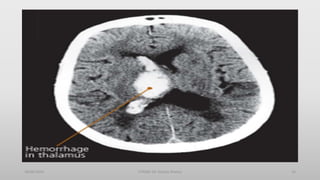

Hemorrhagic Stroke

15% of all strokes

Result from bleeding into the brain tissue

itself

Intracerebral

Subarachnoid

Diagnosis

• CT Scan